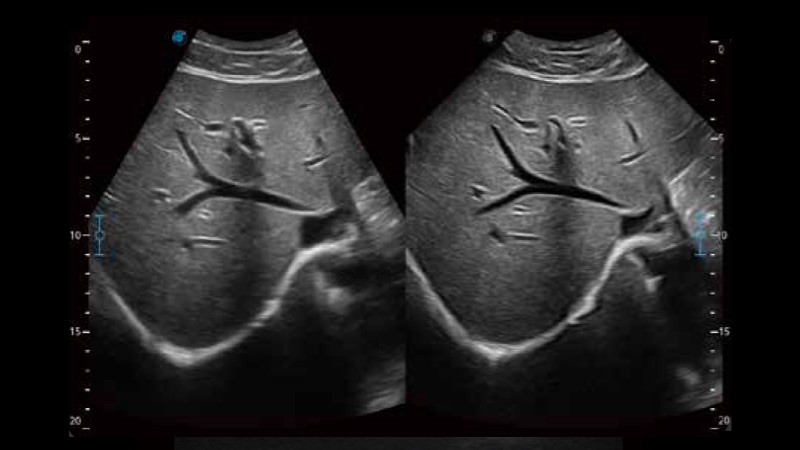

S-Live 高分辨率容积成像

通过仿真成像技术对3D/4D立体数据进行渲染,多种初始光源位置可选,并支持轨迹球360°光源位置自由调节,清晰显示不同方位容积图像细节。